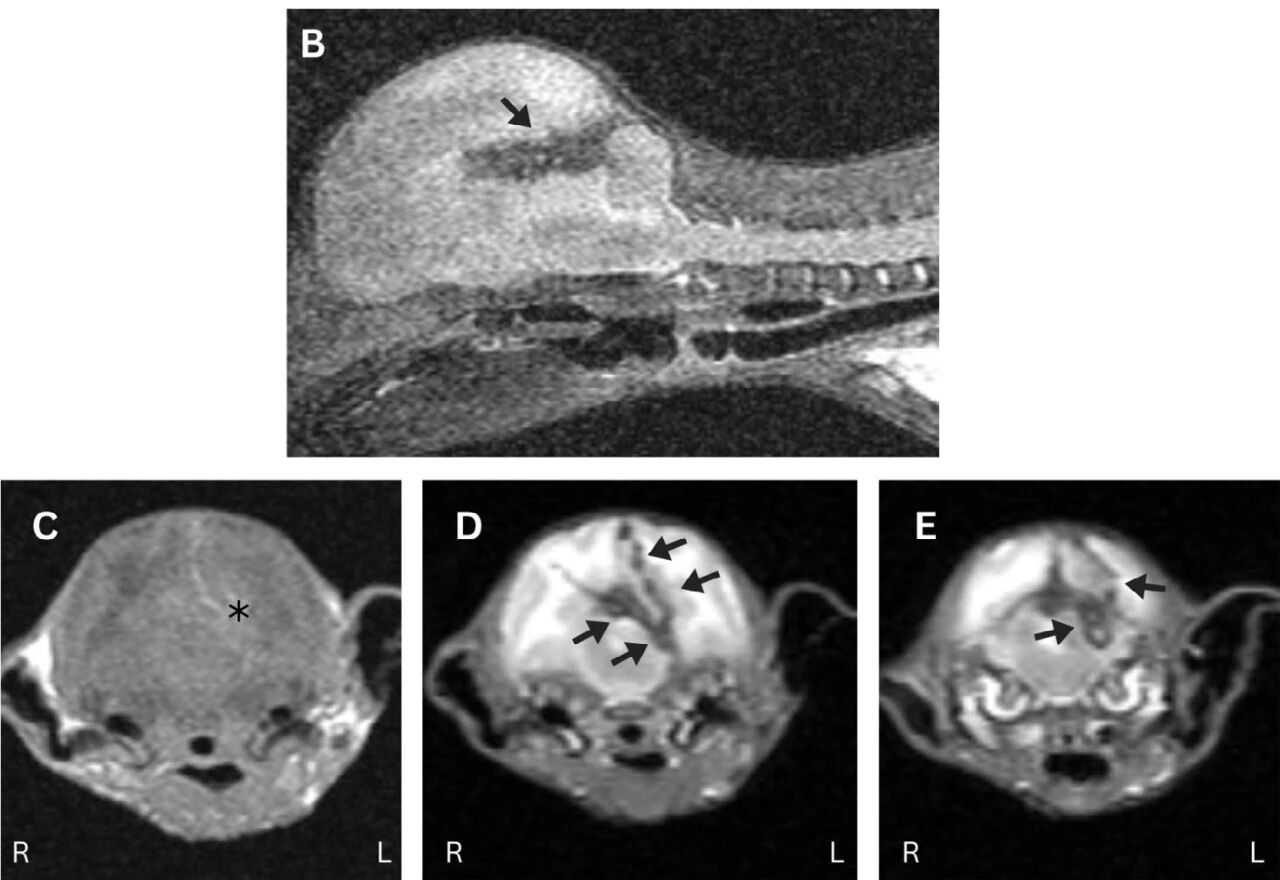

在初次就诊5天后,因疑似呼吸衰竭而心脏骤停,依照主人要求未进行心肺复苏。对大脑进行的死后MRI显示的结果符合脑部异物创伤性插入和移除,包括贯穿右脑半球的出血通道,交叉到左脑半球和小脑幕(下图B–E)。

↑ 在耳鼓泡和小脑幕的水平上获取的T2加权中线矢状图像(B)以及T1加权(C)和T2加权(DE)横断面图像显示出出血路径延伸至右脑半球(C; 星号),穿越中线涉及左脑半球(BD; 箭头)和小脑幕及后颅窝(E; 箭头)。